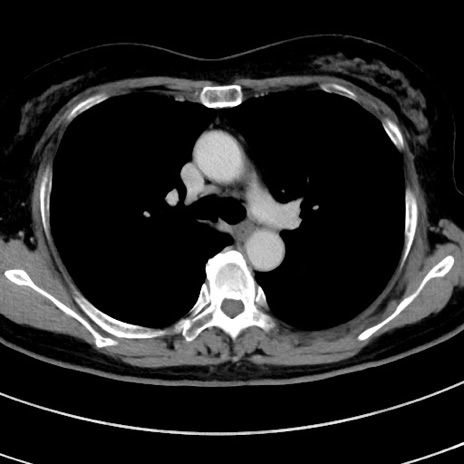

症例9(横断像)

【症例】 60歳代女性

【主訴】むかつき、みぞおちの痛み

【現病歴】3日前よりむかつきがあり、食事がとれない。

【既往歴】糖尿病

【身体所見】発熱なし、心窩部圧痛軽度あるも、腹膜刺激症状なし。

【データ】WBC 7400、CRP 1.92